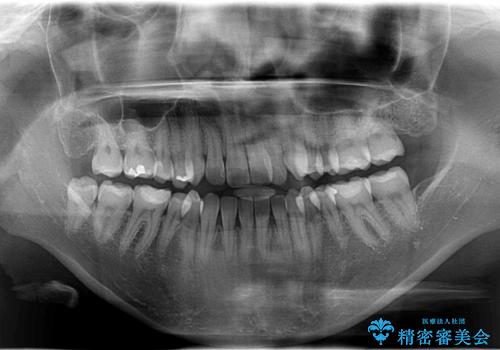

Invisalign インビザライン によるガタつき、受け口傾向の改善

- 拡大・IPRによるスペースゲインを主とした非抜歯・マウスピース矯正を計画しました。

奥歯の位置関係の修正は難儀することが多いマウスピース矯正ですが、割とスムーズに奥歯の位置関係の修正をすることができました。

クロスバイトもきれいになり、きれいな歯並びとなりました。